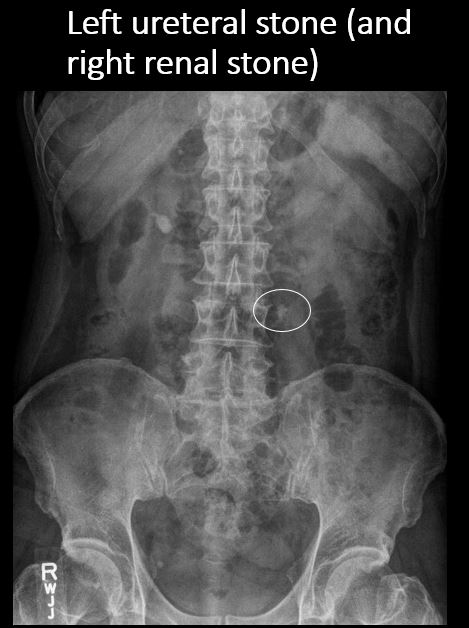

There is a right or left ureteral calcification/stone anywhere from the renal pelvis to the UVJ. |

No | NA |